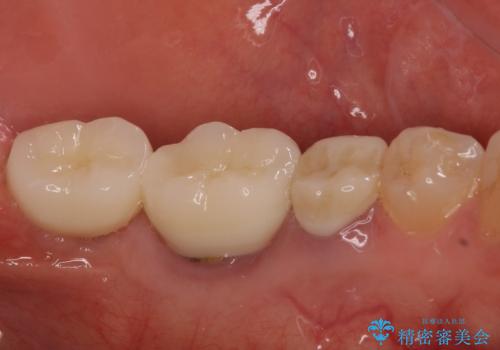

- 抜歯が必要と診断された奥歯の治療を希望して来院された患者様です。

一番奥の歯は歯根の一部を残した状態で、手前の歯とブリッジが装着されていました。

奥歯は歯根周辺の歯槽骨が広範囲に失われており、抜歯が必要と判断されました。

ブリッジの手前側の歯は、根管治療が必要な状態でした。

手前は根管治療後に補綴治療を、奥は骨造成後にインプラント埋入し、手前の歯と同時に補綴治療を行うこととしました。

根管治療と合わせて、穴の開けられている部分を修復したところ、炎症による歯槽骨吸収に改善が見られました。

歯槽骨の高さや幅を回復することができ、望ましい位置にインプラントを埋入することができました。